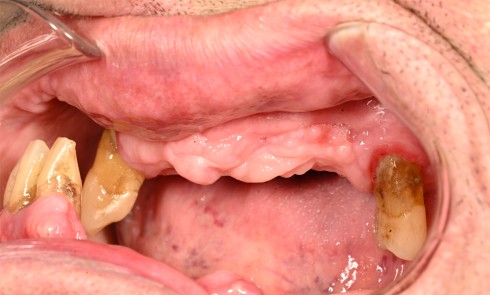

L’édentement partiel constitue un défi majeur dans les réhabilitations prothétiques, tant sur le plan esthétique que fonctionnel. En effet, la...